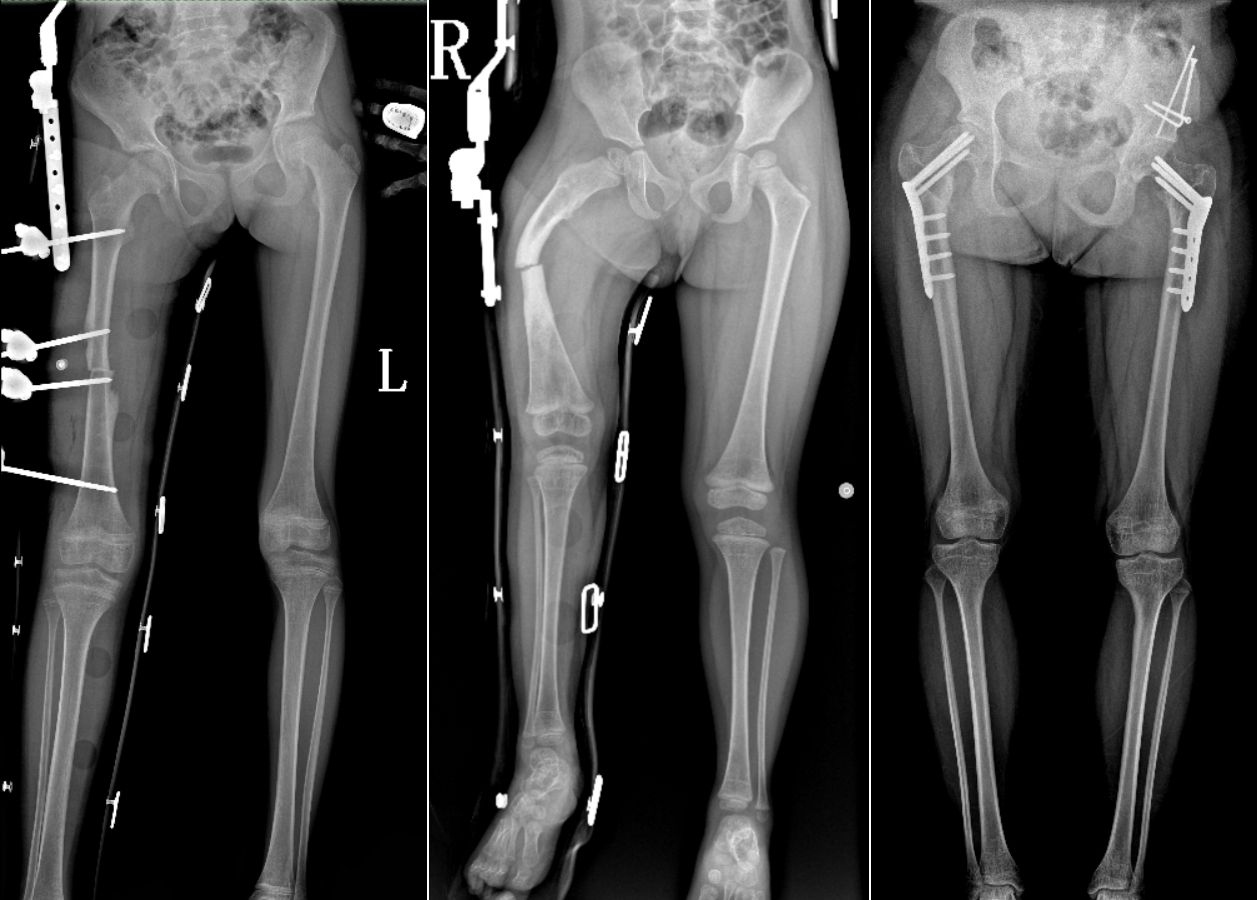

DR是臨床骨科的重要檢查手段之一。在骨科檢查中,脊柱矯形、長(zhǎng)骨骨折、腰椎退行性病變等,需要采集脊柱、下肢全景圖像,輔助醫(yī)生臨床診斷,從而制定科學(xué)的治療方案,普愛醫(yī)療的大視野平板動(dòng)態(tài)DR就像是一座橋梁,連接起現(xiàn)代醫(yī)療技術(shù)與當(dāng)?shù)厝嗣竦尼t(yī)療需求。

普愛醫(yī)療自主研發(fā)的大視野平板動(dòng)態(tài),采用17"*34"的有效視野,一次曝光即可得到全脊柱或全下肢影像。相較于多張攝影再軟件拼接的DR設(shè)備,PLX8600解決了拼接圖像存在密度不均勻,拼接處圖像配準(zhǔn)和放大效應(yīng)等問題,給臨床帶來了真正的大視野影像解決方案。